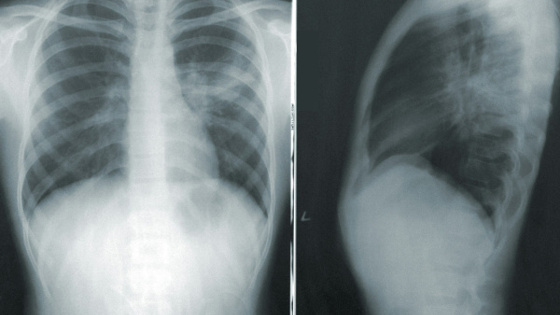

Что входит в состав жидкостей для вейпов? Классический рецепт чаще всего "радует" пропиленгликолем, глицерином, никотином и разнообразными ароматическими добавками. При нагревании смесь выделяет токсические соединения. Как болезнь EVALI влияет на организм? По словам доктора медицинских наук Заура Шугушева, у пациентов, страдающих от нее, стремительно меняется легочная ткань. Все это происходит из-за воспаления, которое вызвано вдыханием токсических веществ, травмами или инфекционными заболеваниями. К чему может привести болезнь вейперов? В первую очередь EVALI способна вызвать синдром острой дыхательной недостаточности (ARDS). Врачи Ирина Окольникова и Алексей Хухрев предупреждают, что смертность в процентных показателях достаточно высока - от 30 до 50. При данном синдроме легкие перестают насыщать кровь кислородом. Такое состояние требует подключения человека к искусственной вентиляции легких. А в центре гигиенического образования населения Роспотребнадзора (ЦГОН) объяснили, что от вейпов в легкие попадают масла, которые провоцируют липоидную пневмонию, которая представляет смертельную опасность для человека. Симптомы болезни EVALI Они во многом похожи на коронавирусную инфекцию. Пациенты чаще всего жалуются на общую слабость, повышенную температуру, кашель и одышку. Однако, в отличие от COVID-19, у данного заболевания одним из первых симптомов является нарушение пищеварительной системы. Выявить патологические изменения можно после проведения компьютерной томографии. История возникновения EVALI В Министерстве здравоохранения РФ рассказали, что изучение болезни от вейпа и электронных сигарет замедлилось из-за пандемии коронавируса, когда симптомы были очень похожи. Впервые ее диагностировали в 2019 году в США. Заболеванию дали название EVALI (от E-cigarette and Vaping use-Associated Lung Injury), что дословно переводится как "Повреждение легких, связанное с употреблением электронных сигарет и вейпа". За последние пять лет в Америке, по официальным данным, от EVALI погибли 68 человек, еще 3 000 пострадали, а сотни стали инвалидами на всю жизнь, сообщает Forbes. Также известно, что в России запретят жидкости с добавками для вейпов.